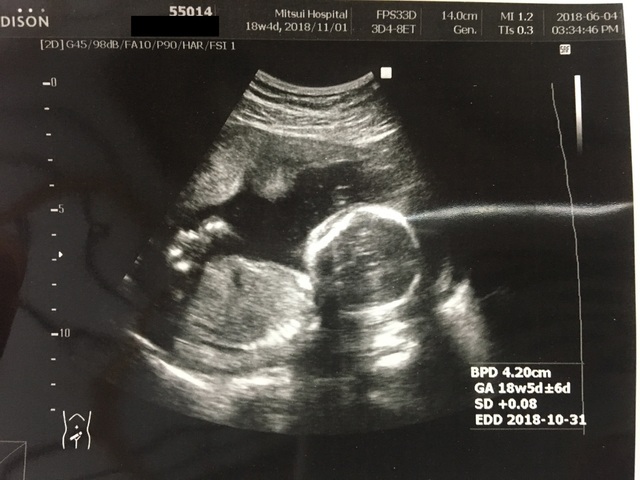

18週4日(18w4d・女の子)|桐 さん(28歳)

エコー写真撮影時のエピソード:

最初のエコー写真は、点しか写ってなくて少しずつ人の形になっていく事にとても感動した! 応募したエコー写真は、全体が写った最後の写真!

次から身体の一部ずつしか写らなくなってお腹の中に命がもう1つあるんだなと成長してるんだなと不思議な気持ちです。